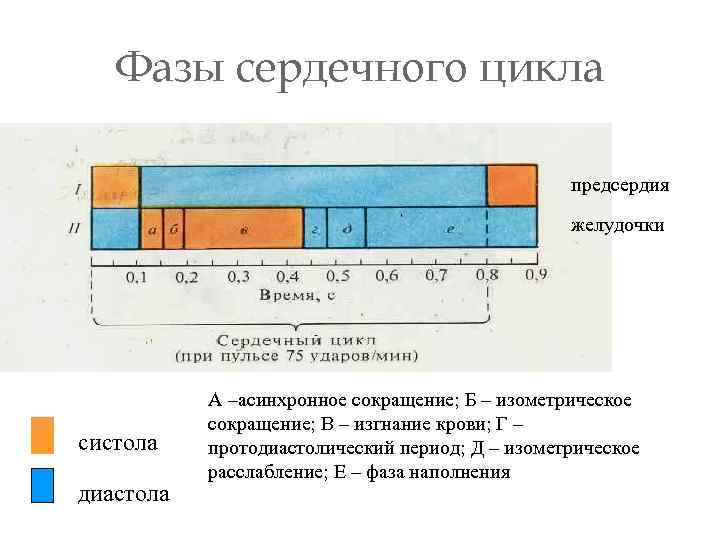

Фазы сердечного цикла предсердия желудочки систола диастола А –асинхронное сокращение; Б – изометрическое сокращение; В – изгнание крови; Г – протодиастолический период; Д – изометрическое расслабление; Е – фаза наполнения

Фазы сердечного цикла предсердия желудочки систола диастола А –асинхронное сокращение; Б – изометрическое сокращение; В – изгнание крови; Г – протодиастолический период; Д – изометрическое расслабление; Е – фаза наполнения

Фазы сердечного цикла Предсердный цикл: - Систола предсердий – 0, 1 с - диастола предсердий – 0, 7 с Желудочковый цикл: - Систола желудочков – 0, 33 с - фаза напряжения – 0, 08 с -период асинхронного сокращения 0, 05 с -период изометрического сокращения – 0, 03 с - фаза изгнания – 0, 25 с -период быстрого изгнания – 0, 12 с -период медленного изгнания – 0, 13 с -Диастола желудочков – 0, 47 с - фаза расслабления – 0, 12 с -протодиастолический период – 0, 04 с -период изометрического расслабления – 0, 08 с - фаза наполнения – 0, 35 с -период быстрого наполнения – 0, 08 с -период медленного наполнения – 0, 17 с -пресистола – 0, 1 с

Фазы сердечного цикла Предсердный цикл: - Систола предсердий – 0, 1 с - диастола предсердий – 0, 7 с Желудочковый цикл: - Систола желудочков – 0, 33 с - фаза напряжения – 0, 08 с -период асинхронного сокращения 0, 05 с -период изометрического сокращения – 0, 03 с - фаза изгнания – 0, 25 с -период быстрого изгнания – 0, 12 с -период медленного изгнания – 0, 13 с -Диастола желудочков – 0, 47 с - фаза расслабления – 0, 12 с -протодиастолический период – 0, 04 с -период изометрического расслабления – 0, 08 с - фаза наполнения – 0, 35 с -период быстрого наполнения – 0, 08 с -период медленного наполнения – 0, 17 с -пресистола – 0, 1 с